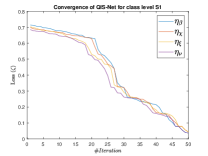

The suitable tailoring of the phase angle in the Hadamard gate advocates the stability of the QFS-Net or its convergence which is very crucial for self-supervised networks where the loss function (here error function) is dependent on the interconnection weights. Hence, the phase angles are evaluated using and as given in Equations 18 and 21, respectively. It is worth noting that the qutrit based quantum neural network provides faster convergence compared to the classical neural networks. This is due to the fact that whereas the classical neural networks are formed using the multiplication of input vector and the weight vector guided by an activation function, the quantum-based networks incorporate the frequency components of the weights and their inputs thereby enabling faster convergence of the network states. This inherent novel feature of the quantum neural networks facilitates the qutrit based fully self-organized quantum algorithm to be employed in QFS-Net to converge super-linearly, as shown in Figure 3. The loss function cum QFS-Net network error function is defined on quantum measurement in the following way.

| (37) |

where, represents the true interconnection weight terms of the inter-connection weights as expressed using the Hadamard gate () at an instance (). is a coherent error function of and . Convergence analysis of the proposed qutrit-inspired QFS-Net is provided in Appendix Section -A and demonstrated experimentally with qubit embedded QIS-Net [39] as shown in Figure 3. It can be summarized that the convergence of the QFS-Net is faster than that of the QIS-Net and also follows super-linearity. This claim is also substantiated by the number of iterations required to converge for each image slice in QFS-Net and QIS-Net as illustrated in Figure 4.